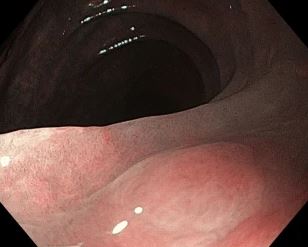

大腸のMALTリンパ腫の多くは、内視鏡ではリンパ腫とは診断されず、生検あるいはポリペクトミーで診断されている

こちらのサイトより引用させていただきました

51名の大腸MALTリンパ腫のうち、最初から内視鏡でリンパ腫が疑われたのは、僅か7名で、16名には「上皮性腫瘍と診断されポリペクトミーが施行された」とあります。

「ポリープ様の大腸MALTリンパ腫」の予後は極めて良好であり、最近は手術や化学療法・放射線をしなくても「内視鏡切除(ESD、EMR)」だけで十分なのではないか?という報告が見られます。限局性の胃のMALTリンパ腫は抗生剤(ピロリ菌の除菌)だけで様子を見るのが第一選択となっており(無効なら放射線を追加する)、大腸も限局性なら内視鏡切除で十分なのではないか?という意見です。血液学の分野では、以前から「くすぶり型/白血病・骨髄腫」と呼ばれていた疾患(経過観察が原則です)と同じであるという意見です。